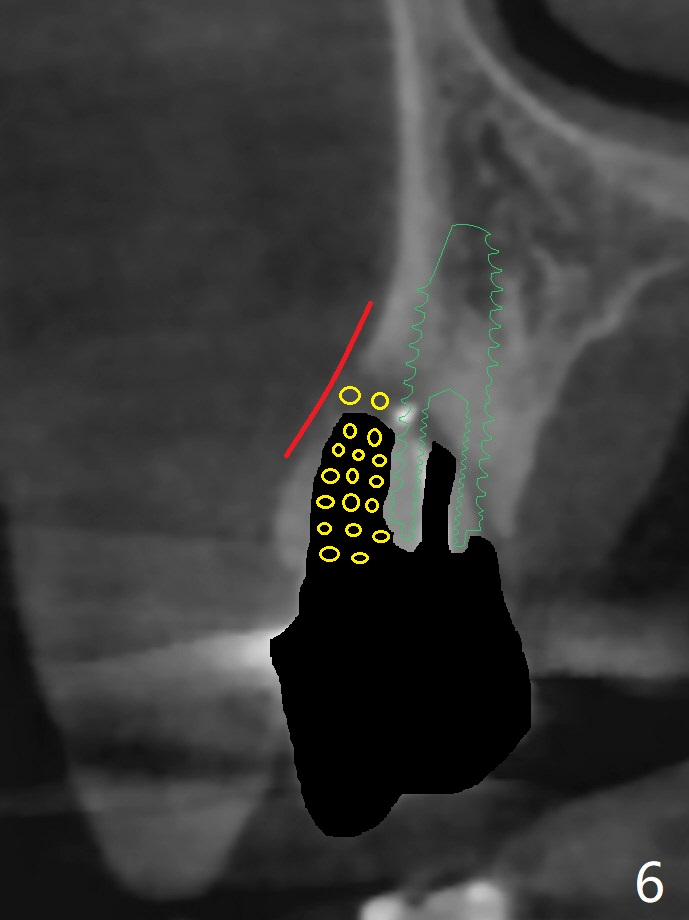

A 74-year-old woman is concerned about buccal fistula of the tooth #5 (Fig.1,2 >). It seems to be safe to place an immediate implant without too much possibility of developing periimplantitis in the future (Fig.3). With guide, restoration could be finished with a 15 degree angled abutment. Remove granulation tissue from the buccal fistula and from the socket. Place a piece of PRF membrane externally (tunnel incision, Fig.4-6 red line) or internally (from the socket) before bone graft (before and after implant placement (Fig.5,6 yellow circles)). Take 5x5 cm CT immediately postop to confirm the repair.